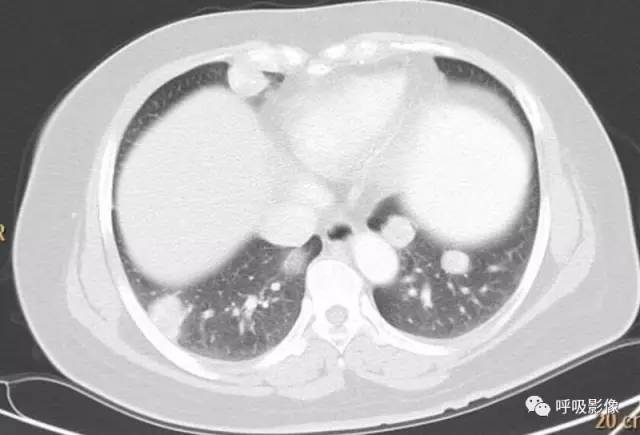

转移灶的影像早期可表现为不规则的小片状影或磨玻璃样阴影,逐渐增密、增粗,形成边缘不光滑的结节或肿块影,可伴出血,此时边缘毛糙,周围出现晕征、铺路石征等(图2)。

注意绒毛膜癌肺转移可以表现为单发。出血、晕征可以是早期表现。

图2 女,39岁 绒癌双肺转移伴肺内出血。可见肺内磨玻璃影和铺路石征。